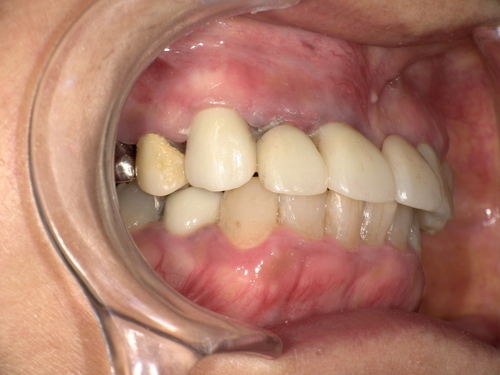

口の中に白っぽい「線状・網目状・斑点状」の病変が現れ、粘膜が硬く、時に痛みやヒリヒリ感、赤みを伴います。病変部がむずがゆい、物を噛むときに不快感がある、口内炎が繰り返すような感覚が現れる方も多いです。

白く盛り上がった粘膜(網目状または板状)

赤みを伴う潰瘍状の病変

歯の詰め物(金属・銀歯)や薬剤の影響

古い銀歯や金属製クラウンから金属イオンが溶出し、口腔粘膜との接触でアレルギー反応が生じる場合があります。クロム・ニッケル・金・水銀などが原因物質となることがあり、金属アレルギーのある人は特に注意が必要です。